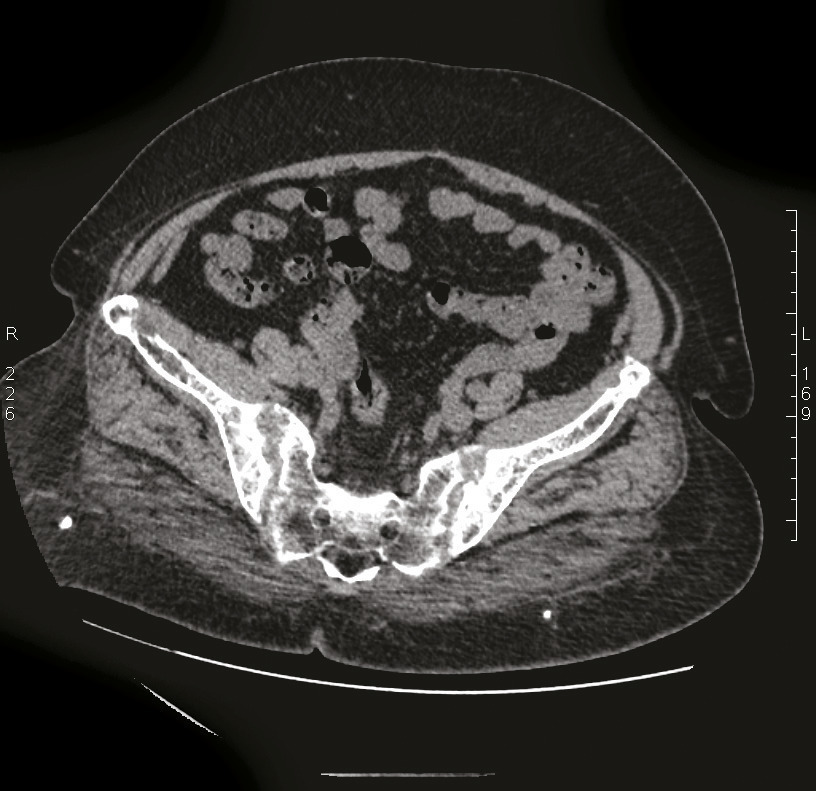

Cette patiente congolaise de 61 ans consultait pour des douleurs lombaires mécaniques anciennes très invalidantes. Les radiographies montraient une déminéralisation osseuse diffuse. La tomodensitométrie du bassin montrait une ostéolyse très particulière des deux sacro-iliaques (fig. 1) ainsi que des lésions fibrokystiques de l’aileron sacré droit (fig. 2). La calcémie était à 3,81 mmol/L, la parathormone était à 1 300 pg/mL (N : 6-50 pg/mL) confirmant le diagnostic d’hyperparathryoïdie primaire. La scintigraphie parathyroïdienne localisait une formation macronodulaire intensément fixante de 30 mm de grand axe au pôle inférieur du lobe thyroïdien droit (fig. 3). La patiente bénéficiait d’une parathyroïdectomie inférieure droite sous anesthésie locale, la calcémie se normalisait en 15 jours et les douleurs s’amélioraient en 3 mois.

Les lésions osseuses de l’hyperparathyroïdie primaire1 sont classiquement une ostéoporose et plus rarement une résorption sous-périostée des os longs ou de la symphyse pubienne, voire des sacro-iliaques (fig. 1). On peut observer des géodes ovalaires (fig. 2) disséminées (ostéite fibro- kystique de von Recklinghausen) avec des déformations osseuses. Après traitement, il est généralement observé une régression de l’ostéopénie et une persistance des lésions kystiques.